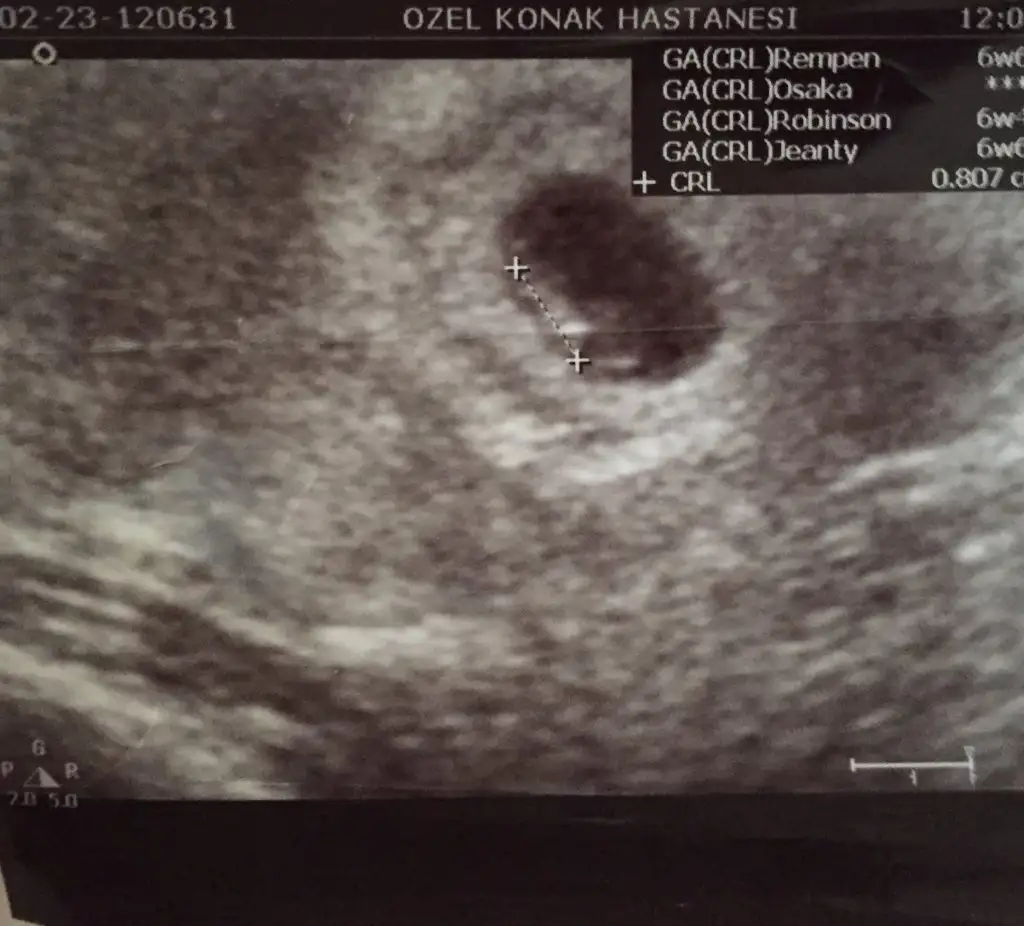

Solda erkek canin...6 haftalık...

Resimde saga az bisey daha yakin canim saga yakin olumca kiz deniyo ac haftaluk 8 varmi ?? ama kesenin seklide fasulye seklinde ozaman da erken deniyo .. bilemedim yuzde 51 kiz 49 erkek ..ikisi de sağa mi yakın. Birde sağ derken ultrasonda mi sağ yoksa karında mi sağ

Iki ultrasonda farklı aynı kişiye ait değil ilk resim 7+2 kinci resim 7+4Resimde saga az bisey daha yakin canim saga yakin olumca kiz deniyo ac haftaluk 8 varmi ?? ama kesenin seklide fasulye seklinde ozaman da erken deniyo .. bilemedim yuzde 51 kiz 49 erkek ..

Canim nerde oldunu belli deil sanki solda yukarda bo belirti var ama kesenin sekli yuvarlak olunca kkiz deniyo .. daha cok erken canom bidaki resim e bakip bida yorum yapalim :))Kızlar yolladım sonunda burda 5*6 haftalıktı....tek resimde bu bişey gorunuyomu yada netarafta